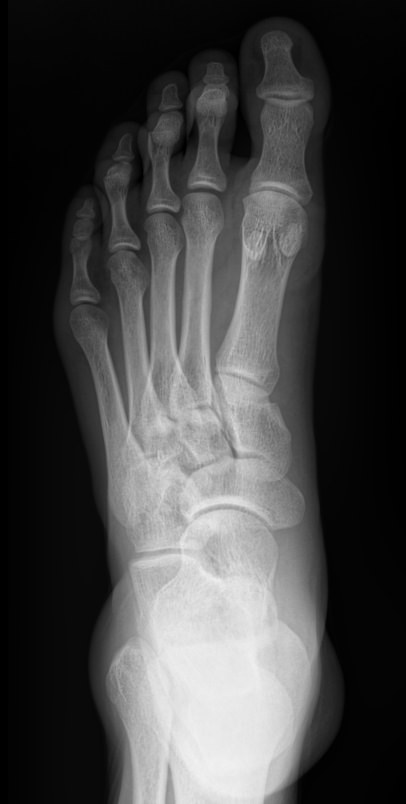

В качестве диагностической процедуры для выявления плоскостопия часто используют рентген. Прицельное исследование стопы позволяет увидеть изменения в ее строении, а также вычислить угол и высоту свода стопы, показатели которых используются для установления стадии болезни.

На снимке будут отчетливо видны:

• Кости предплюсны;

• Наложенные друг на друга кости плюсны;

• Травмы, в том числе застарелые;

• Патологические изменения видимых суставов;

• Опухоли.

Рассчитывается высота и угол свода стопы и соответствующая им степень плоскостопия.